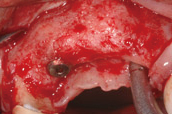

骨脊增厚術,利用骨粉、再生膜等生物科技材料,放入骨脊內,促進缺損處的骨頭再生的術式。先把骨粉放到欲填補的缺損處,然後使用再生膜隔絕表皮軟組織細胞的生長,讓骨粉有時間可以轉化成新生骨。等待約6個月讓骨頭生長,就可以重建喪失的齒槽骨寬度了!